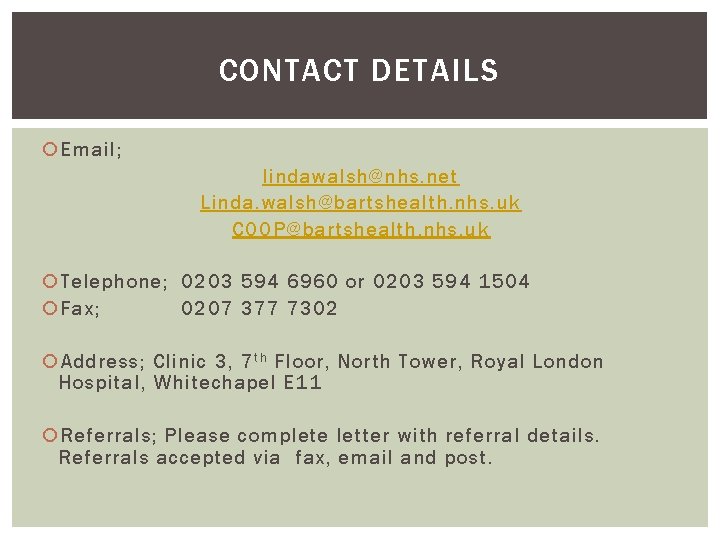

CONTACT DETAILS Email; lindawalsh@nhs. net Linda. walsh@bartshealth. nhs. uk COOP@bartshealth. nhs. uk Telephone; 0203 594 6960 or 0203 594 1504 Fax; 0207 377 7302 Address; Clinic 3, 7 t h Floor, North Tower, Royal London Hospital, Whitechapel E 11 Referrals; Please complete letter with referral details. Referrals accepted via fax, email and post.